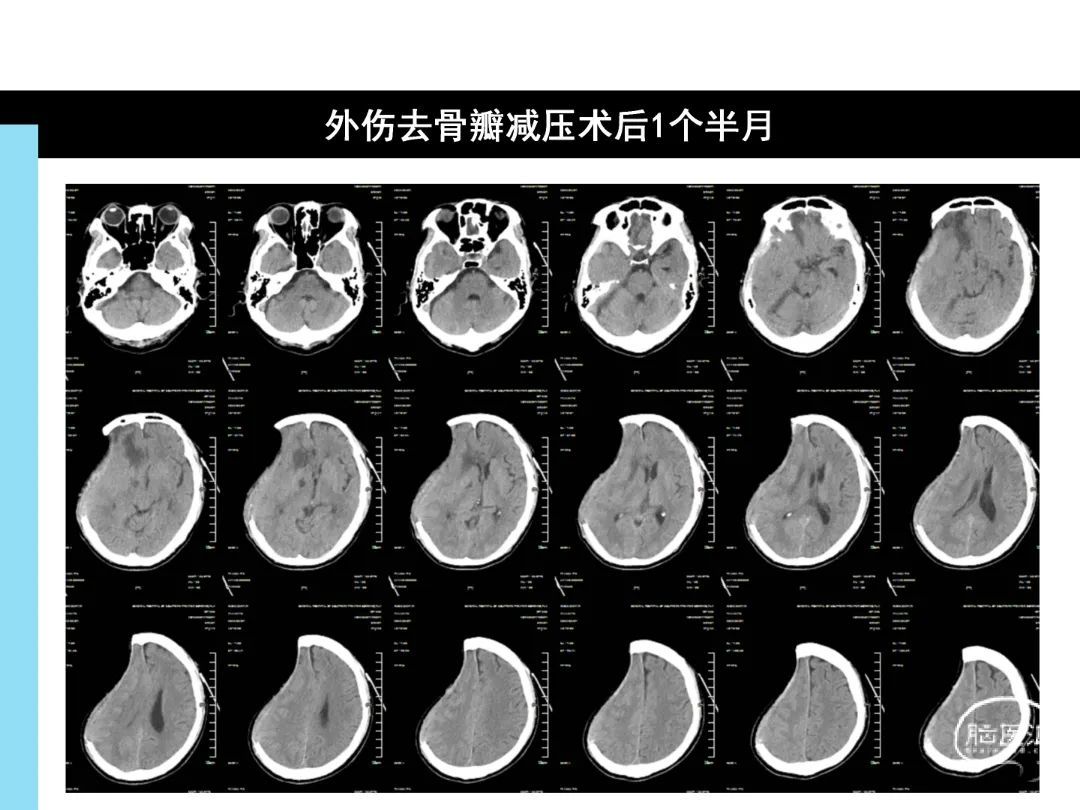

去骨瓣减压术后反常性脑疝